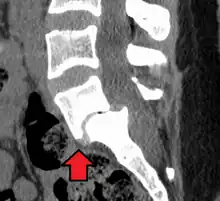

| X-ray of the lateral lumbar spine with a grade III anterolisthesis at the L5-S1 level. | |